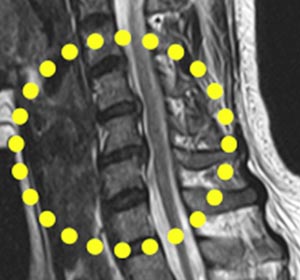

목은 목뼈(경추) 7개로 되어 있다며 뼈와 뼈 사이에 디스크가 있습니다. 디스크는 기립 자세에서 수직으로 끼치는 압력을 분산하고 목이 동작할 때 관절 역할을 합니다. 나이가 들면 아무라도 피부 탄력이 감퇴하여 주름이 생기듯 척추의 디스크도 수분 함유하고 있는 분량이 쇠퇴하여 긴장되고 이로 인하여 충격을 섭식하고 압력을 분산시켜서하는 기능이 저하되요.

목디스크는 왜 생기는 걸까요? 사람들이 나이가 들면 디스크의 수분 성분인 수핵의 수분함유 분량이 떨어뜨리여 탄력이 감소하게 되고 해로운 자세나 사고 등의 바깥 부분적인 자극에 의해 디스크가 밀려나 목디스크 질환의 이유가 되는 것이 된다고 합니다. 평범할 때 생활하면서 틀린 습관, 목에 가해진 충격 등에 의해 일어나기 쉽다고 하고요.